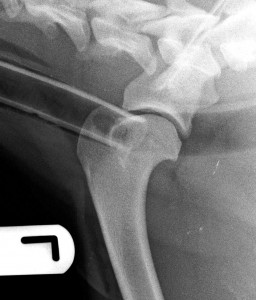

Shoulder OCD is often apparent on simple x-rays. The possibility of OCD being present can be investigated with contrast x-rays or arthroscopy. It can be treated with arthroscopy or open surgical management,. Cartilage fragments and flaps are removed. The site from which the cartilage originated can be encouraged to fill will with fibrocartilage by creating forage holes with a fine drill/pin, and recruiting a blood supply from the underlying humeral head.